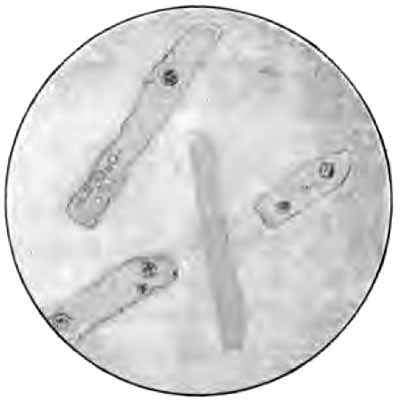

Elastic fibers from the sputum

FIG. 4.—Elastic fibers from the sputum: a, Highly magnified; b, alveolar arrangement, less highly magnified (after Bizzozero).

1. Elastic Fibers.—These are the elastic fibers of the pulmonary substance (Fig. 4). When found in the sputum, they always indicate destructive disease of the lungs, provided they do not come from the food, which is a not infrequent source. They are found most commonly in phthisis: rarely in other diseases. Advanced cases of tuberculosis often show great numbers, and, rarely, they may be found in early tuberculosis when the bacilli cannot be detected. In gangrene of the lung, where they would be expected, they are frequently not found, owing, probably, to the presence of a ferment which destroys them.

[p. 28] The fibers should be searched for with a two-thirds objective, although a one-sixth is needed to identify them with certainty. Under the one-sixth they appear as slender, highly refractive fibers with double contour and, often, curled or split ends. Frequently they are found in alveolar arrangement, retaining the original outline of the alveoli of the lung (Fig. 4, b). Leptothrix buccalis, which is a normal inhabitant of the mouth, may easily be mistaken for elastic tissue. It can be distinguished by running a little iodin solution under the cover-glass (see p. 37).

To find elastic fibers when not abundant boil the sputum with a 10 per cent. solution of caustic soda until it becomes fluid, add several times its bulk of water, and centrifugalize, or allow to stand for twenty-four hours in a conical glass. Examine the sediment microscopically. [p. 29] The fibers will be pale and swollen. Too long boiling will destroy them entirely.